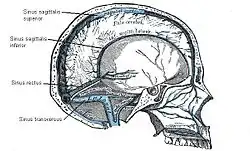

Abflüsse

Das Gehirn besitzt kleine Venolen und Venen wie andere Organe auch, die jedoch unabhängig von den Arterien verlaufen. Sie werden in eine tiefe (Venae profundae cerebri) und eine oberflächliche (Venae superficiales cerebri) Gruppe unterteilt. Die größte Hirnvene ist die nur etwa 1 cm lange Vena magna cerebri (Galeni) unter dem Splenium des Balkens. Das sauerstoffarme Blut wird in anatomisch besonders gebauten Hirnblutleitern, den Sinus durae matris gesammelt: Dabei handelt es sich um Duplikaturen der harten Hirnhaut, die auf der Innenseite mit Endothel ausgekleidet sind. Die Sinus bilden ein miteinander verbundenes System und münden schließlich in die inneren Drosselvenen.